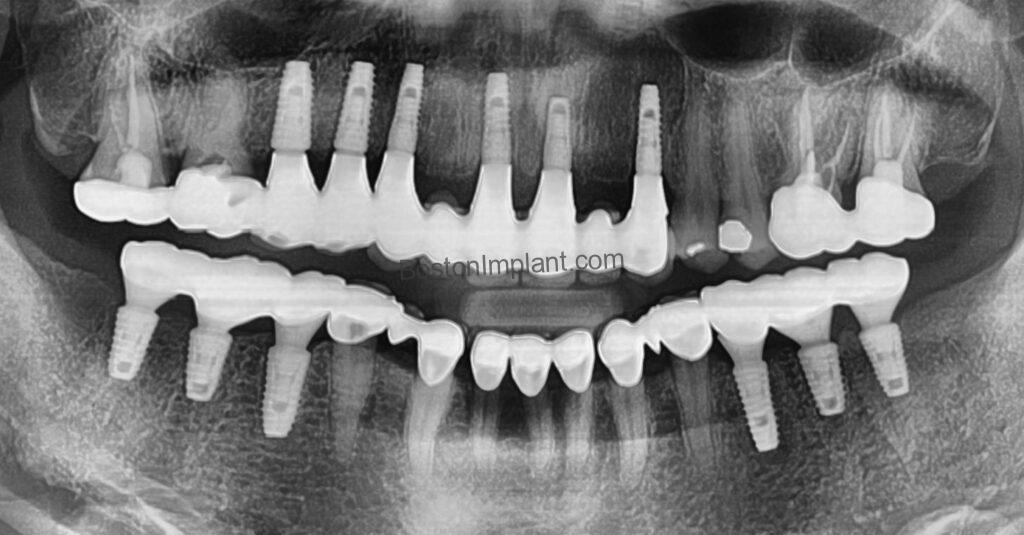

After the osseointegration period, we performed a second, minor surgery to expose the implants and take impressions for her final crowns. For complex cases like hers, I prefer to create temporary crowns first. This allows us to assess the shape, color, and bite, ensuring her complete comfort and satisfaction before fabricating the final restorations.

While the placement of the final crowns marked a significant milestone, achieving optimal function and aesthetics with multiple implants often requires fine-tuning. We scheduled follow-up appointments, making adjustments to ensure a perfect fit and bite. Unlike natural teeth, which can shift over time, implants remain fixed, necessitating these meticulous adjustments.

Today, she has a beautiful, confident smile and a stable, comfortable bite. Despite the two-hour drive, she continues to visit my practice every six months for routine check-ups. It’s a testament to her dedication and our shared commitment to maintaining her oral health and happiness.